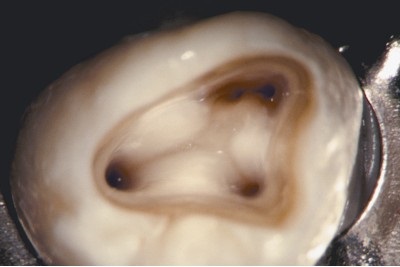

Fișierele ProTaper au fost utilizate pentru tratamentul endodontic al primului molar al maxilarului inferior. Observați patru optim canalul pregătit având curba de mai multe niveluri. (Proprietate Dr. Pierre mast, Paris, Franța)